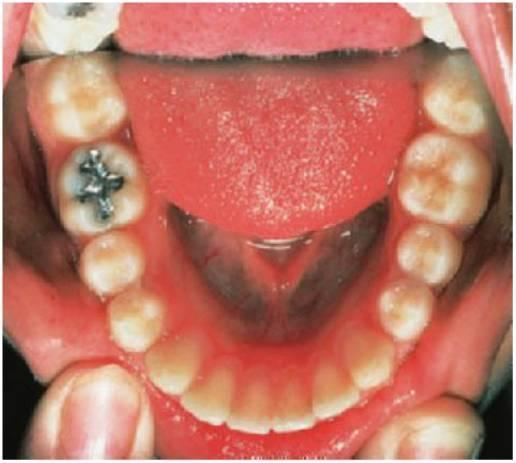

Método para las restauraciones de ionómero de vidrio

- Siempre que sea necesario, infiltrar anestesia local y aislar con dique de goma (fig. 5.3).

- El contorno de la cavidad debe rodear toda la extensión de la lesión cariosa. No es necesaria una extensión por prevención. Tampoco suele ser necesaria una pequeña cola de milano oclusal en las restauraciones interproximales. Sin embargo, la retención de las cavidades proximales mínimas puede conseguirse practicando surcos en la dentina con una fresa redonda muy pequeña (tamaño Yi) (fig. 5.4).

- Eliminar toda la caries blanda con el uso de una fresa redonda a baja velocidad o un instrumento manual. Debe tenerse en cuenta el gran tamaño de la cámara pulpar puesto que es fácil exponer la pulpa de un diente temporal.

- Preacondicionar la dentina mediante el uso de ácido poliacrílico al 10% durante 10 segundos, lavar y secar.

- Cuando se utilicen materiales encapsulados, asegurarse de que las cápsulas se comprimen durante, al menos, 3 segundos para facilitar la mezcla adecuada del polvo y el líquido. Tras mezclarlos durante 10 segundos en el amalgamador, desechar los primeros 3-4 mm del material mezclado puesto que la mezcla no suele ser satisfactoria. Colocar el resto directamente en la cavidad.

- Una vez colocado el material relativamente espeso en la cavidad, comprimir con un bruñidor de bola, humedeciendo ligeramente la punta en una pequeña cantidad de agente adhesivo o de resina sin relleno para evitar que el material se pegue al instrumento.

- Hay que proteger la restauración final de la contaminación por humedad. Como mejor se consigue esto es colocando una fina capa de resina sin relleno sobre la superficie y polimerizándola durante 20 segundos. En niños pequeños con problemas de comportamiento, puede ser más apropiado utilizar vaselina en lugar de resina sin relleno.

- Al retirar el dique de goma, hay que comprobar la oclusión.